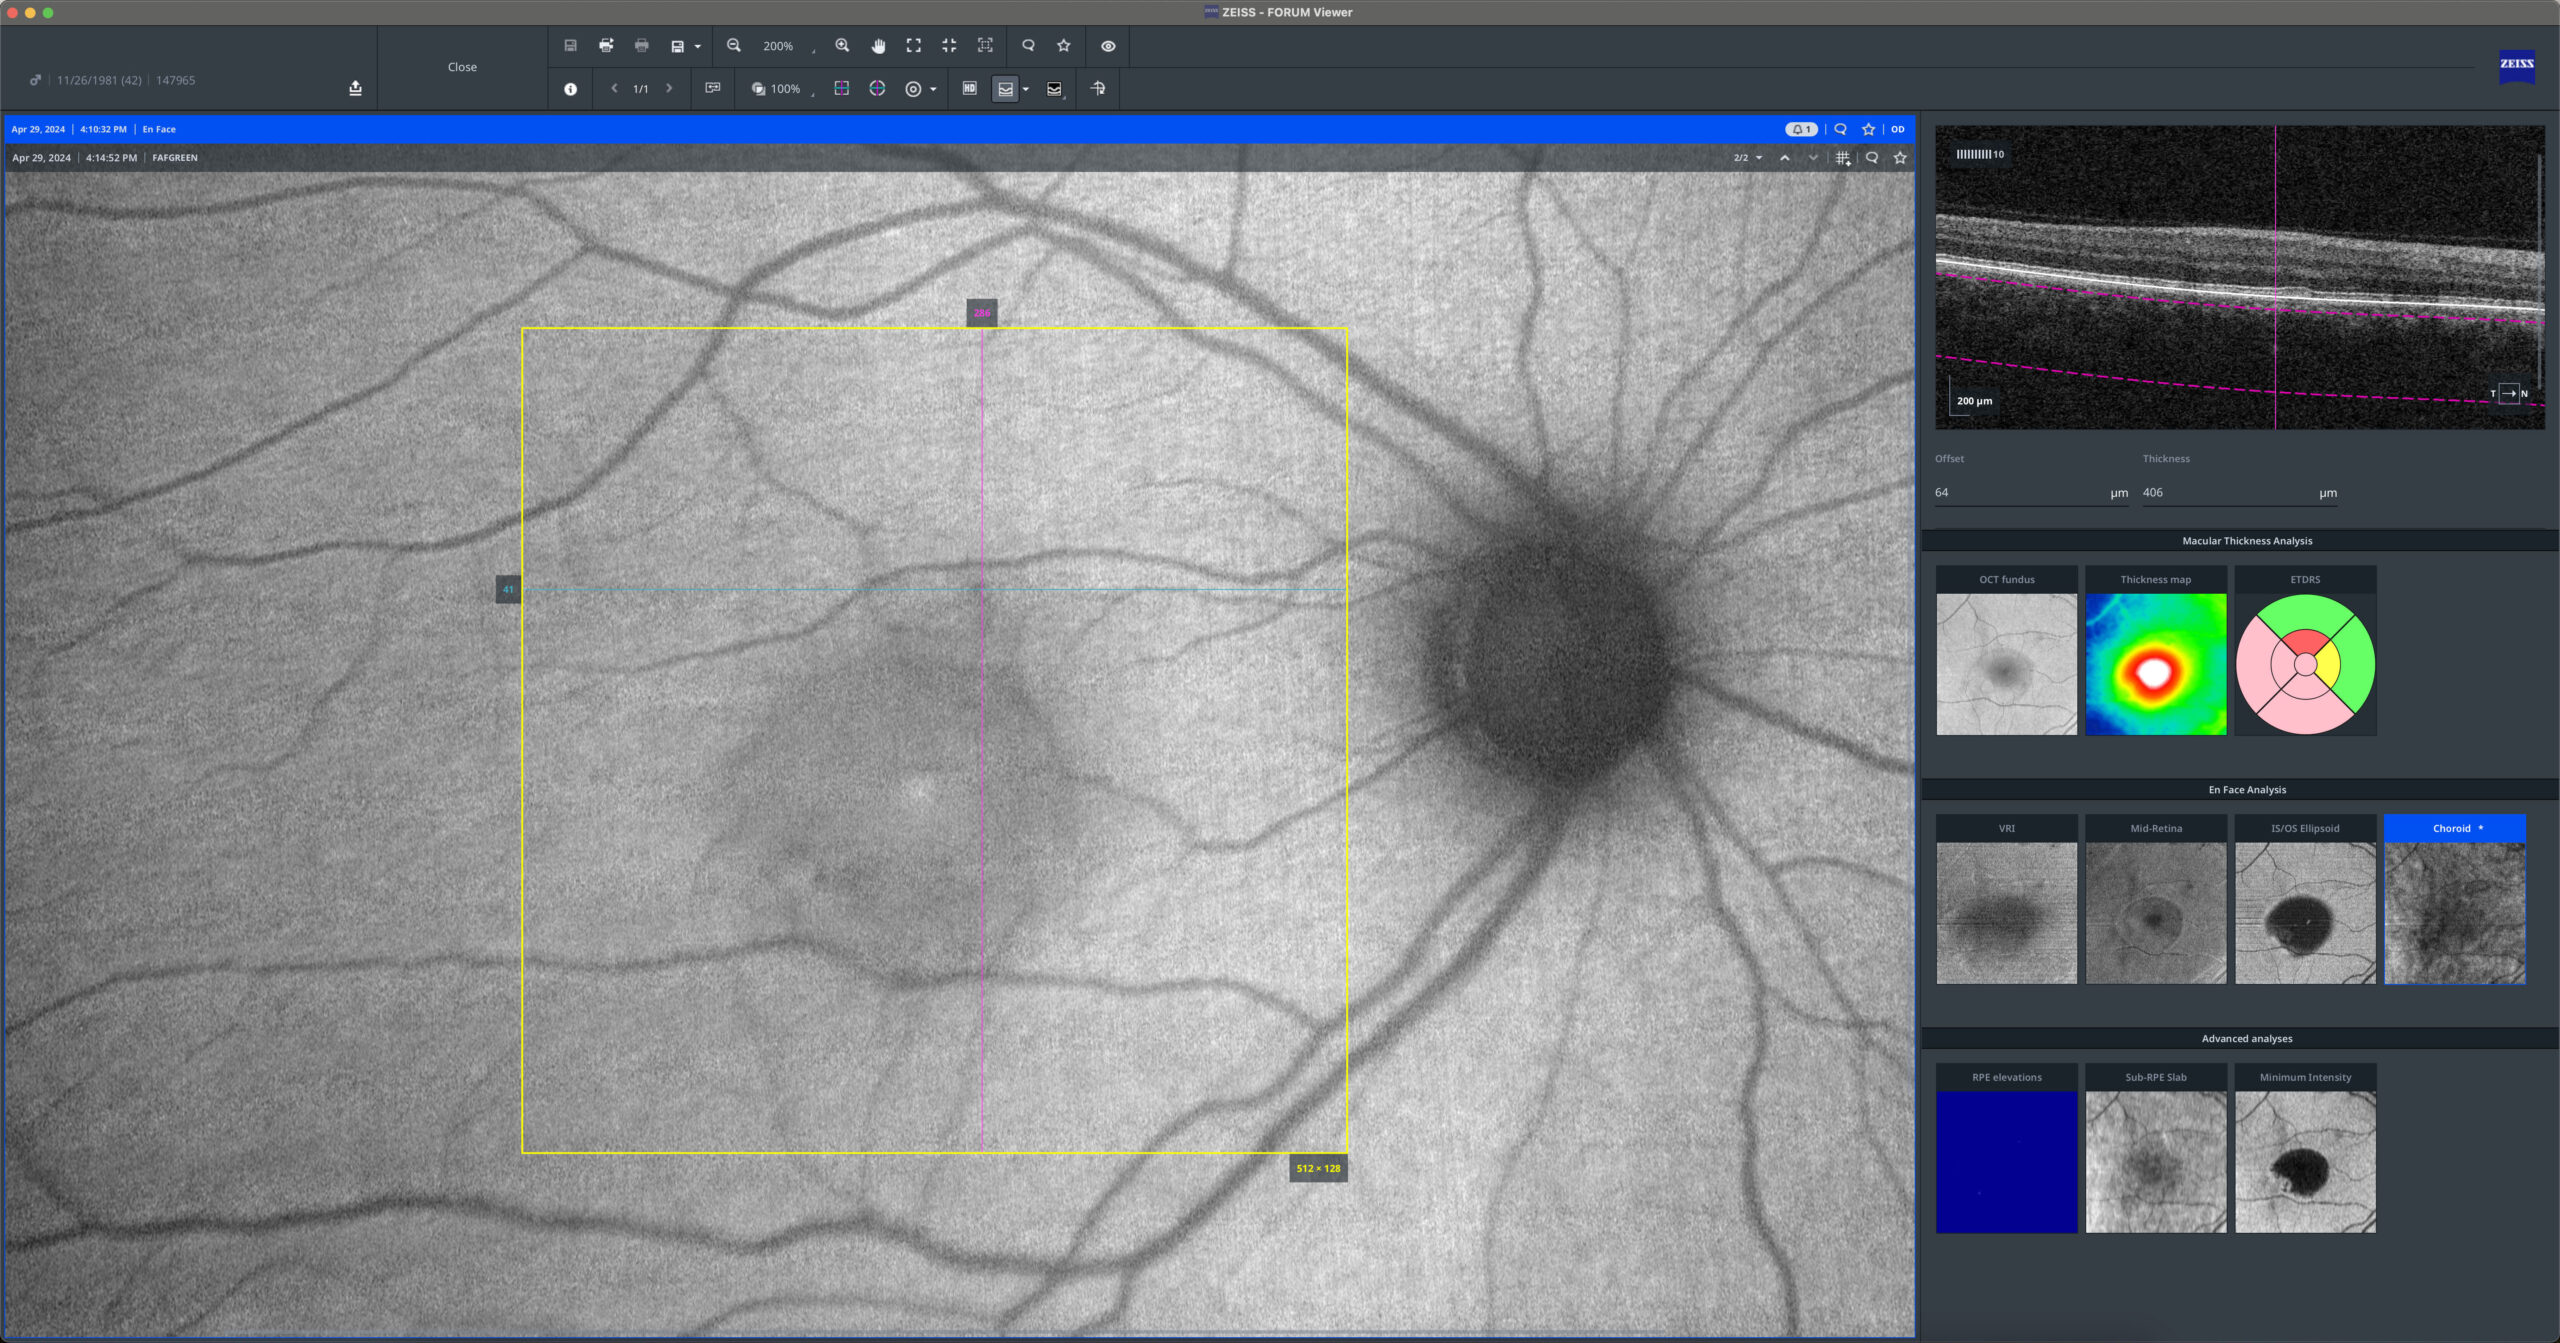

Central Serous Chorioretinopathy

40yo

40yo In Central Serous Chorioretinopathy (CSC), serous retinal detachment and serous pigment epithelial detachment (PED) are hallmark findings. Optical Coherence Tomography (OCT) reveals a hyporeflective space beneath the neurosensory retina and PEDs, often associated with focal RPE abnormalities. The leakage site at the RPE can be identified on OCT as a […]